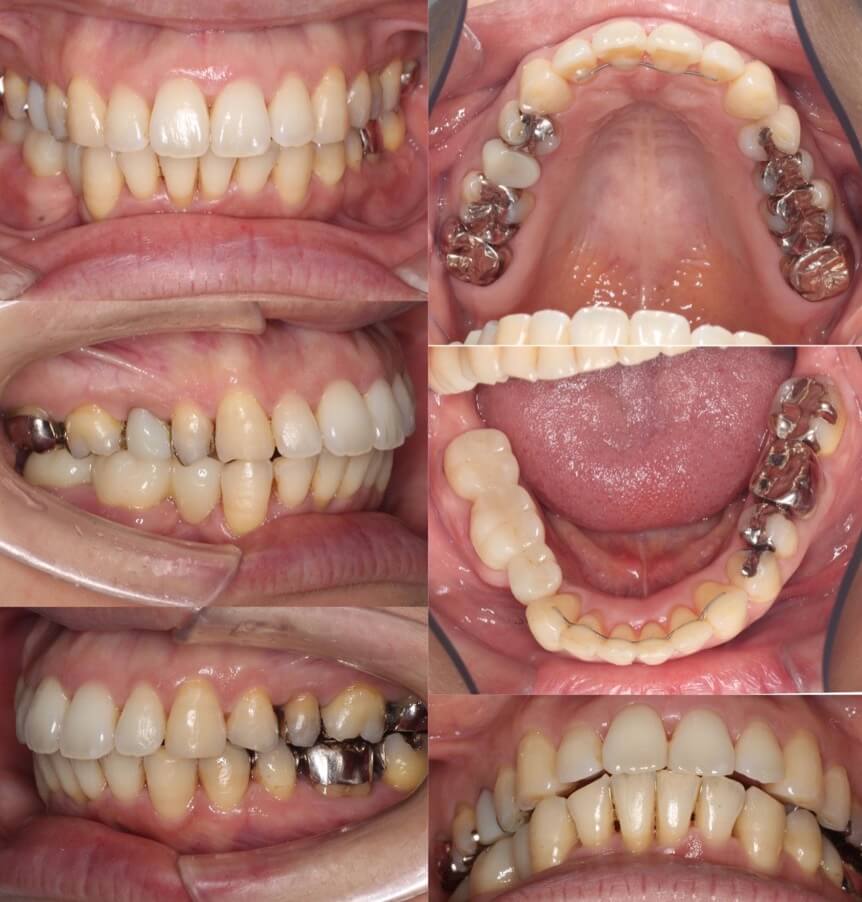

53代女性・ブリッジ補綴・マウスピース型装置

右下が2歯欠損しており、下の歯並びの正中も大きく右にずれているケースです。欠損部はブリッジ補綴を行う予定でしたので、スペースを開きすぎないように注意しながら上下歯列の正中線を近づけました。正中線は多少不一致が残ってしまったのですが、上の前歯も後退し、治療後は良好な歯列とかみ合わせになりました。

<症例概要>

主訴:上の前歯の前突

年齢・性別:50代女性

住まい:千葉県八千代市

症状:右下54番欠損・上顎前突・下顎右偏

治療方針:抜歯空隙閉鎖+下顎前歯唇側傾斜

補綴:右下⑦6⑤ブリッジ(一般歯科依頼)

治療装置:マウスピース型矯正装置(アライナー装置)

治療期間:1年7か月

アライナー枚数:42+31ステージ

リテーナー:上下フィックスタイプ+プレートタイプ

治療費用:990,000(税込)

代表的副作用:痛み・治療後の後戻り・歯根吸収・歯髄壊死・歯肉退縮

▶︎その他の副作用

【治療シミュレーション】

右下の抜歯欠損歯空隙にブリッジを作成できるよう1歯分以上(7.5mm)開かないように設定しました。